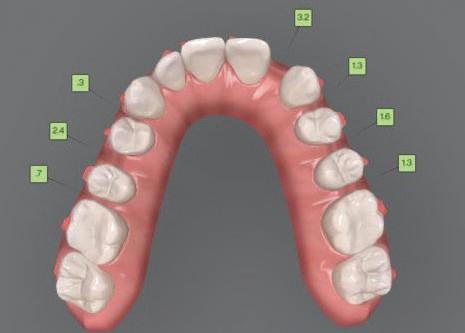

7Dental Tribune Bulgarian Edition / октомври 2022 г. Преди лечението Фиг. 1 Фиг. 4 Фиг. 7 Фиг. 10 Фиг. 13 Фиг. 16 Фиг. 17 Фиг. 18 Фиг. 19 Фиг. 20 Фиг. 11 Фиг. 14 Фиг. 12 Фиг. 15 Фиг. 8 Фиг. 9 Фиг. 5 Фиг. 6 Фиг. 2 Фиг. 3

8 Dental Tribune Bulgarian Edition / октомври 2022 г. По време на лечението Фиг. 21 Фиг. 25 Фиг. 30 Фиг. 31 Фиг. 34 Фиг. 38 Фиг. 40 Фиг. 44 Фиг. 48 Фиг. 50 Фиг. 49 Фиг. 46 Фиг. 39 Фиг. 41 Фиг. 45 Фиг. 47 Фиг. 42 Фиг. 43 Фиг. 35 Фиг. 36 Фиг. 37 Фиг. 32 Фиг. 33 Фиг. 26 Фиг. 28 Фиг. 29 Фиг. 27 Фиг. 22 Фиг. 23 Фиг. 24

9Dental Tribune Bulgarian Edition / октомври 2022 г. След лечението За авторите: Д-р Манол Ивчев е създател на COLDY DENT Functional Atelier, завършва дентална медицина във ФДМ, София. Шест години е стажант в ортодонтска практика. Интересите му са изцяло насочени към функционалната дентална медицина. Посещава курсовете на Доусън и Льо Гал. Преминава редица обучения, акредитирани от Института на Славичек във Виена – VieSID. Впоследствие става най-младият инструктор във VieSID. Придобива права да преподава философията на проф. Рудолф Славичек в България. В практиката си се придържа към протоколите на Славичек за функционално лече ние и диагностика, тъй като те са насочени към комплексно лечение. Завършва всички нива за морфология на зъбите и моделаж при Janos Mako. Повишава знанията си по функционална ортодонтия чрез индивидуален курс в Румъния. Д-р Ивчев е и сертифициран зъболекар по лингвална ортодонтия от Катедрата по ортодонтия от Университета по стоматология в Тегу, Южна Корея. Сертифициран е и за лечение на ортодонтски аномалии чрез миофункционални апарати, а също и за ортодонтия, подпомагана от миниимпланти, отново от Университета по стоматология в Южна Корея. Завършва индивидуално обучение по функционална ортодонтия в Университета по дентална медицина в Богота, Колумбия, както и индивидуално обучение по функционална ортодонтия и физиотерапия по про токола на Mariano Rocabado. Има завършено индивидуално обучение по функционална зъботехника и функционален Wax-Up клас I,II и III. Завършва курс за Digital Smile Design и Skin Concept в Люксембург при Christian Coachman, Florin Cofar, Paulo Kano, Josef Kunkela, Livio Yoshinagа. Зт. Leandro Gambogi, Бразилия, завършва зъботехника през 1999 г. Експерт и пионер в дигиталната диагностика. Лектор и инструктор на курсове в областта на дигиталното протезиране. Понастоящем е главен изпълнителен директор и зъботехник в DENTALE DIGITAL LAB. В периода януари 2005 г. – декември 2006 г. завършва бизнес управление и администрация в Methodist University Center Izabela Hendrix. Съавтор на книгата Odontologia Digital: Desafiando os Limites, глава 5: „Дигитално включване във времето. Технология CAD/CAM“. Преминал множество обучения при световноизвестни кли ницисти. Фиг. 51 Фиг. 54 Фиг. 57 Фиг. 58 Фиг. 63 Фиг. 64 Фиг. 65 Фиг. 59 Фиг. 61 Фиг. 62 Фиг. 60 Фиг. 55 Фиг. 56 Фиг. 52 Фиг. 53 Фиг. 66